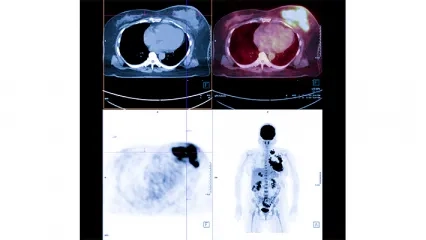

Radyoloji , Girişimsel Radyoloji

Nükleer Tıp , Tiroid - Paratiroid Hastalıkları ve Cerrahisi Kliniği